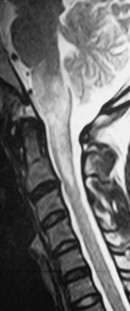

NMOSD MOG Ab Disease Sarcoidosis Paraneoplastic Dural AVF Cord Infarction Cervical Spondylosis